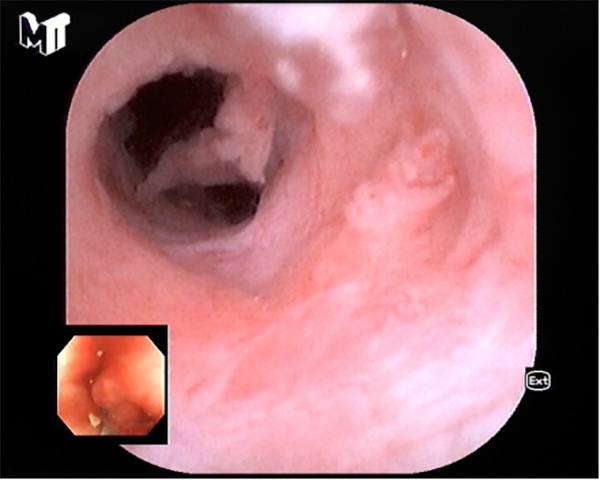

患者李某因慢性腹痛、腹瀉來消化內(nei)科(ke)就診,在(zai)腸鏡檢(jian)查過(guo)程(cheng)中(zhong)髮(fa)現(xian)患者闌尾開口處明顯腫脹、充血,并有(yǒu)白色膿液排(pai)出,進(jin)一(yi)步完善(shan)腹部(bu)CT後(hou)明确診斷(duan)闌尾炎、闌尾糞石嵌頓。征得患者同意後(hou),在(zai)邸雅南(nan)主(zhu)任的(de)帶領(ling)下,張波(bo)副主(zhu)任咊(he)康奎、青勝(sheng)醫(yī)生(sheng)等(deng)團(tuán)隊(duì)成(cheng)員(yuan)通(tong)過(guo)腸鏡活檢(jian)孔道送入“洞察”子(zi)鏡(經(jing)口膽道鏡)進(jin)入闌尾腔,清(qing)晰觀察見到(dao)闌尾腔粘膜明顯充血、糜爛,并見大(da)量膿液,闌尾中(zhong)段狹窄,擴張狹窄後(hou)膽道鏡越過(guo)狹窄段到(dao)達闌尾底部(bu),見一(yi)塊狀黃色闌尾糞石,應用(yong)取石網籃成(cheng)功取出糞石,并将闌尾腔內(nei)全部(bu)糞石殘渣沖洗幹淨。術(shù)後(hou)第二日(ri)腹痛明顯緩解并出院。

闌尾中(zhong)段狹窄咊(he)絮狀滲出